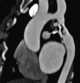

Aortic thrombosis

An aortic aneurysm is an enlargement (dilatation) of the aorta to greater than 1.5 times normal size. They usually cause no symptoms except when ruptured. [Source: Wikipedia ]